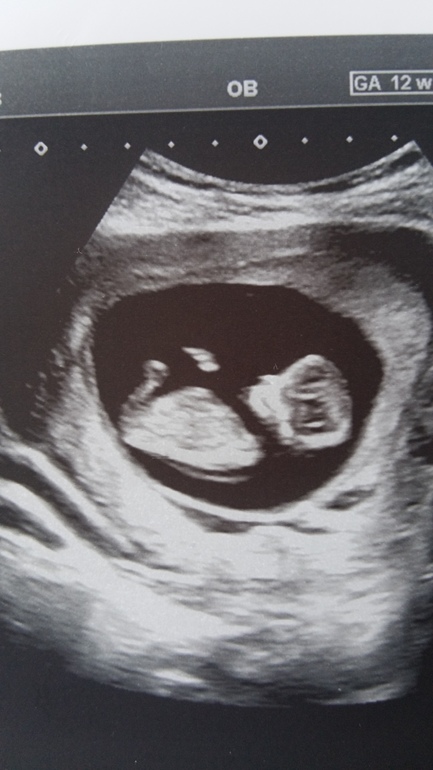

Пол малышаДевочки, сегодня была на первом скрининге...дали снимочек. Я бугорок разглядела🤗🤗🤗Но интересно совпадет ли моё мнение) Как думаете мальчик или девочка?😉

Спасибо большое за Ваш комментарий) Я тоже сдавала кровь на определение пола, показал, что должна быть девочка. А узист предположил на 80%мальчик на 12 неделе по виду "снизу"...а гинеколог говорит, на этом сроке с низу все "мальчики" и по этому ракурсу определить нельзя...только по наклону полового бугорка....ну вот через 10 дней пойду на УЗИ и уже думаю узнаем, кто же в домике живёт😉

По-моему на этом фото бугорка вообще не видно, ножки же закрывают. Где вы разглядели.

По моему это бугорок😉